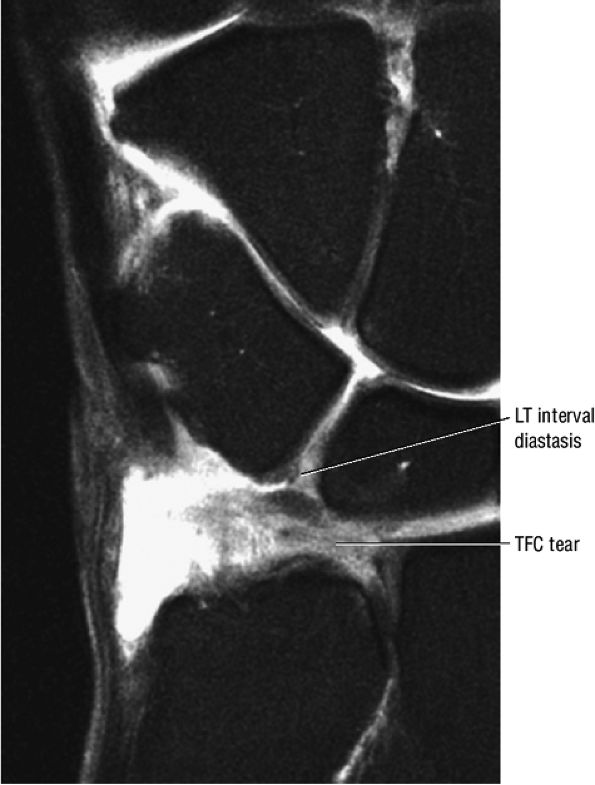

|

FIGURE 10.36 Triangular Fibrocartilage.

ulnar styloid can chronically impact the proximal triquetrum.